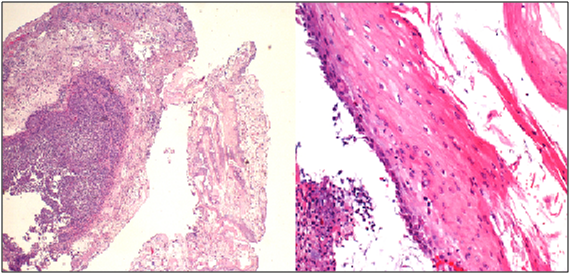

A 46 year-old male with end stage renal disease underwent deceased donor kidney transplant followed by immunosuppression with MMF, tacrolimus, and prednisone. Shortly after transplantation, he noted new solid food intermittent dysphagia with slow progression over 6 months. He was later hospitalized with progressive worsening of nausea, vomiting and dysphagia. Esophagogastroduodenoscopy (EGD) showed LA Class D esophagitis about 10 cm above the gastro-esophageal junction with a stenosisat 30cm from the incisors. Biopsies showed acute and chronic inflammation without increased eosinophils or evidence of Barrett’s mucosa. Stains for fungi, cytomegalovirus (CMV) and herpesvirus (HSV) were negative. He was treated with esomeprazole 40mg twice a day but was re-hospitalized one month later with persistent symptoms. A repeat EGD demonstrated once again LA Class D esophagitis with worsening stricture in the proximal part of the lower third of the esophagus along with candida plaques. Biopsies revealed severe esophagitis without CMV/HSV (Figure 1). The stricture was dilated up to 44 Fusing Maloney dilators and fluconazole and nystatin were added to his proton pump inhibitor (PPI).

Figure 1 20x (left) and 40x (right) views of desquamated squamous epithelium with associated acute fibrino-inflammatory infiltrates consisting predominantly of neutrophils with background reactive cytologic changes.

Despite the increasing recognition of MMF-induced GI tract mucosal injury, we are reporting the first clinical case of circumferential esophagitis with stricture of which we are aware. The pathologic changes observed included inflamed, necrotic squamous cells, fibrino-inflammatory exudates and fibrin deposits in the ulcer bed, but unlike many patients with small bowel or colonic damage from MMF, they did not have the mucosal features often characteristic of GVHD. Cessation of mycophenolate and dilation of the esophageal stricture led to complete clinical, radiographic, and endoscopic resolution. Moreover, the lack of symptomatic recurrence in the absence of PPI therapy for the following several years further supports MMF-induced esophageal injury as the etiology. In conclusion, a diagnosis of MMF-induced esophagitis, while rare, should be considered in a patient with dysphagia when more common etiologies have been excluded or when esophagitis is PPI refractory. Pathologic findings include desquamated squamous epithelium with fibrino-inflammatory exudates, granulation tissue, and neutrophilic infiltrates. Unlike small bowel and colonic mucosal injury from MMF, microscopic changes may not reflect findings similar to GVHD. MMF-related esophageal mucosal injury resolves with discontinuation of the immunosuppressant.